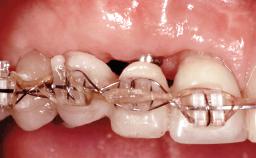

A 30-year-old woman was referred by her general dentist for evaluation of an esthetic complication related to previous implant treatment for congenitally missing maxillary lateral incisors. The patient’s chief complaint was the inadequate esthetic appearance of her smile. The case demonstrates the use of a combined approach to achieve optimal results. Two different flap designs - a tunnel technique and a coronally advanced flap - are employed based on the surgical objectives for the affected site.

Soft Tissue Grafting Yes